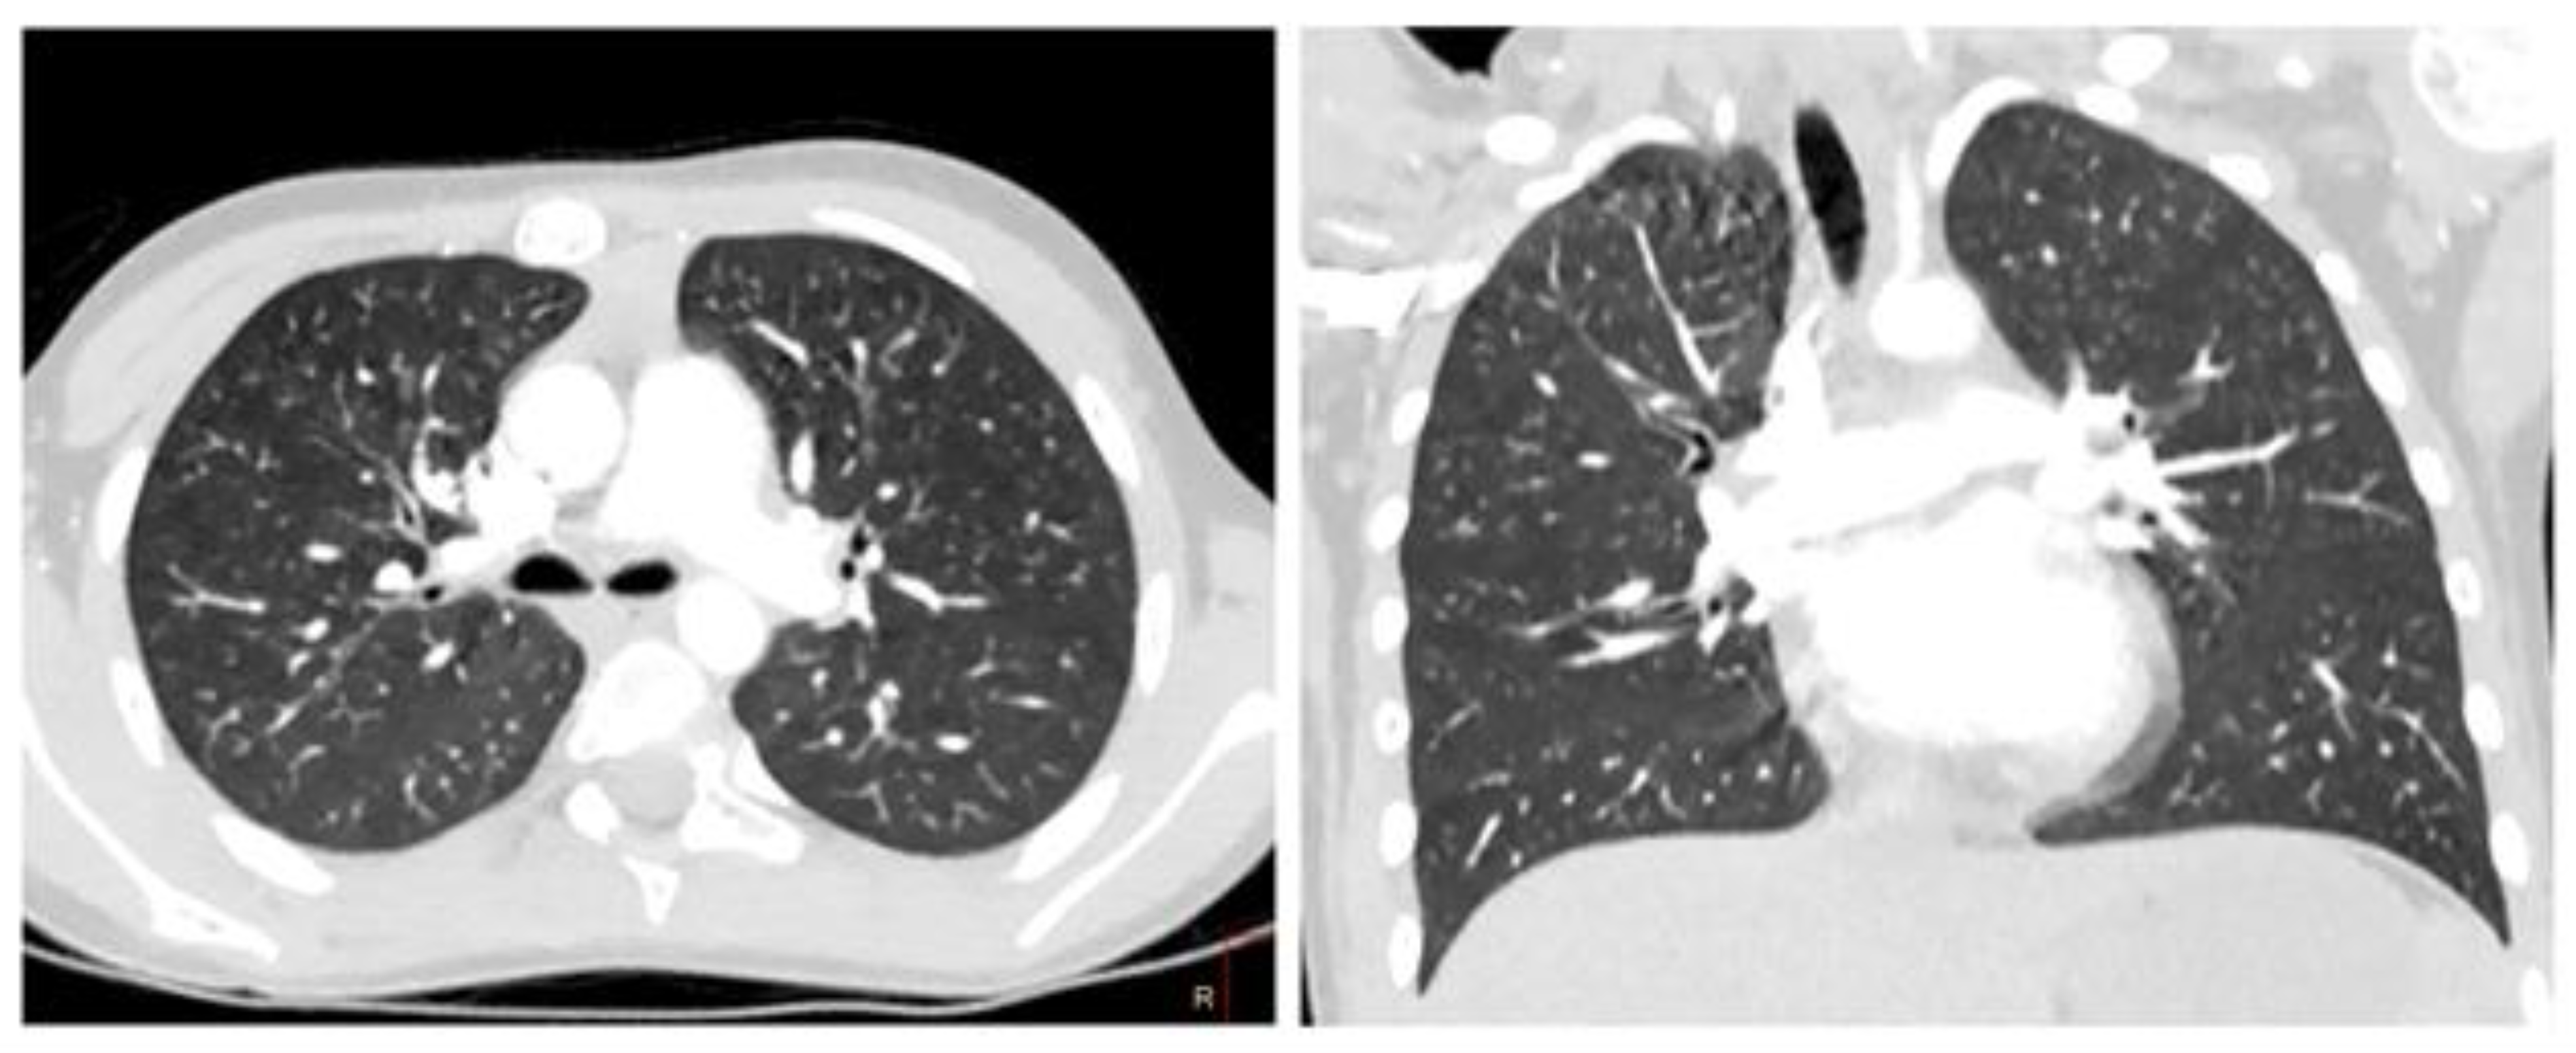

The data of the chest computed tomography (CT), including contrast agent for determination of vascular thrombosis, are shown in Figure 4.

Figure 4.

Heart CT angiography, axial plane, and pulmonary regimen in a 7-year-old child. (A) Reduction in lung pneumatization due to extensive confluent ground glass attenuation. (B) Free fluid was determined in the pleural cavities on both sides.

The CT and CT-angiography, a diffuse decrease of the lung pneumatization was diagnosed due to extensive confluent “ground-glass” attenuation, and free fluid up to 25 and 30 mm was determined in the pleural cavities on the right and left, respectively. The signs of left-sided thromboembolism of subsegmental branches of the A8 pulmonary artery and heterogeneity of pneumatization were diagnosed (Figure 4).

Heart CT, axial and coronal angiography, and pulmonary mode after 4 weeks.